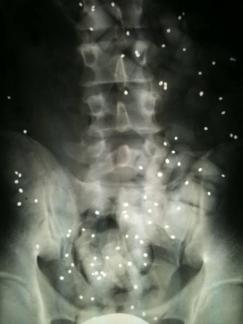

Wie wichtig sind Röntgenbilder?

Röntgenbilder sind wichtig, aber häufig überbewertet.

Wenn keine Hinweise auf eine scherwiegende Erkrankung (spezifische Rückenschmerzen) vorliegen dann ist die genaue Befragung und die Untersuchung wichtiger als Röntgenbilder.

Wenn Sie Röntgenbilder mitgebracht haben werden wir und diese gemeinsam mit Ihnen anschauen.

Nicht selten erwidern Patienten auf die Frage, was sie zu uns führt, mit der Antwort: "Schauen sie die Bilder an, ich habe 3 Bandscheibenvorfälle!".

3 relevante Vorfälle sind selten und solche Aussagen kommen zustande, wenn die Röntgenbefunde fehlinterpretiert werden.